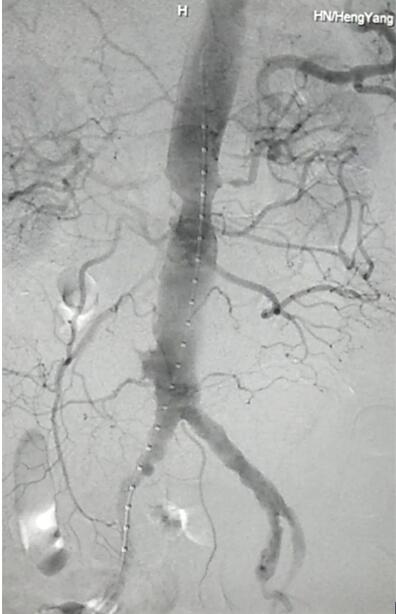

通訊員張永明報(bào)道:4月20日,在李珍發(fā)博士的帶領(lǐng)下,衡陽(yáng)市中心醫(yī)院血管介入科專家涂宏手術(shù)小組成功為一位86歲高齡的李爺爺行腹主動(dòng)脈覆膜支架隔絕術(shù)血管介入治療,為患者排除體內(nèi)定時(shí)炸彈。

患者因腹部搏動(dòng)性腫塊行成已有4年,伴右下腹疼痛6小時(shí)入院,既往有高血壓病史,患者入院后血壓177/96mmHg,醫(yī)護(hù)人員隨即予以控制血壓、止痛處理,CTA檢查提示患者有腎下腹主動(dòng)脈瘤,合并心 、肝 、肺 、腎等重要臟器疾患,根據(jù) Laplace定律,動(dòng)脈瘤直徑越大壓力越大,老人動(dòng)脈脆弱,動(dòng)脈瘤隨時(shí)有破裂的可能性,其危險(xiǎn)性大。血管介入科排除各種困難,在麻醉科協(xié)作下行腹主動(dòng)脈瘤覆膜支架隔絕術(shù)(“褲衩”支架植入),手術(shù)持續(xù)了1個(gè)半小時(shí),患者術(shù)后安返病房,麻醉醒后露出了微笑,向醫(yī)務(wù)人員伸出大拇指。

CTA檢查提示患者有腎下腹主動(dòng)脈瘤。